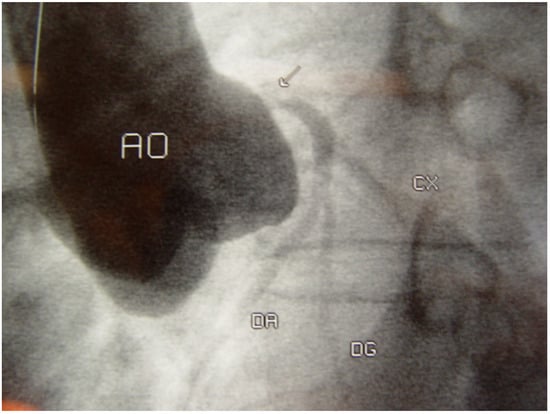

Case Description